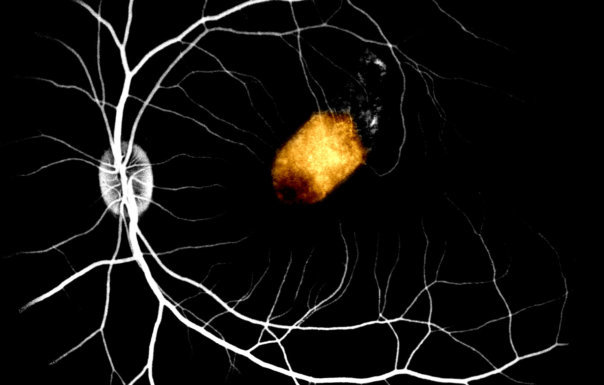

Eye Stem Cells Transplanted From Corpses Could Cure Blindness

Researchers say retina cells from a corpse continue to survive after being transplanted into the eyes of monkeys.

By Study Finds     Image Credit: Icahn School of Medicine at Mount Sinai

Now, a new study finds stem cells taken from deceased patients may also help in creating a cure for blindness.

Retinal pigment epithelium (RPE), a layer of cells in the eyes, transports nutrients and waste products to and from the retina.

These cells also act as a barrier and help regulate light receptors, all of which are “essential” for normal vision.

Now, for the first time, scientists have successfully produced retina cells in monkeys using human stem cells.